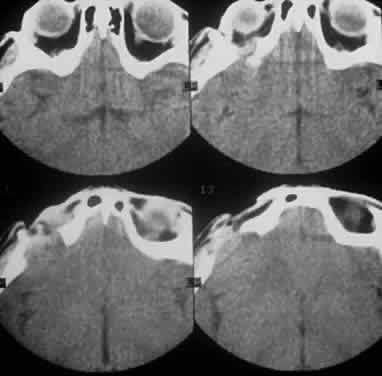

Systemic non-Hodgkin's lymphomas usually present with painless lymph node enlargement in one or more nodes. Adults usually are in their fifth or sixth decade, and presentation in childhood is extremely rare. The fever, night sweats, and weight loss characteristic of Hodgkin's disease generally are absent. Splenomegaly may develop in 20% of patients. Patients usually have normal blood counts, although they may develop lymphocytosis, especially with well-differentiated lymphocytic lymphomas, or pancytopenia with anemia, hemorrhage, petechiae, ecchymosis, and infection—the pancytopenia occurring in one third of patients as a result of bone marrow involvement or chemotherapy and radiation. Patients with B-cell lymphomas tend to develop difficulty with bacterial infection, whereas those with T-cell lymphoma may develop difficulty with delayed-type hypersensitivity and viral infections. Leukemic conversion is rare in adults, although it occurs in 25% of children. In children, an acute leukemic phase may be the initial presentation. Furthermore, children are more likely to develop extranodal and aggressive disease, although they may respond well to therapy.50 In a series of 1269 patients, of whom only 3 (0.42%) presented initially with proptosis, one third of patients presented with extranodal disease and a few with bone marrow invasion.51 There was a 1.3% incidence rate of orbital disease secondary to systemic lymphoma.